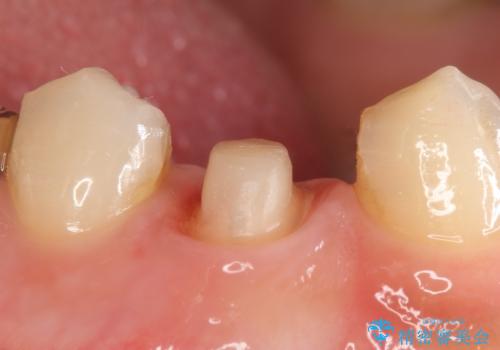

- 右下4番目の歯でものを咬むと疼くような痛みがあるといらっしゃった方の症例です。

X線上で根尖病変を認めたため再根管治療を行い、症状改善後、オールセラミッククラウンによる補綴を行いました。

- オールセラミッククラウン(st)…¥100,000、仮歯…¥10,000、ファイバーコア…¥20,000費用は治療当時の料金となります